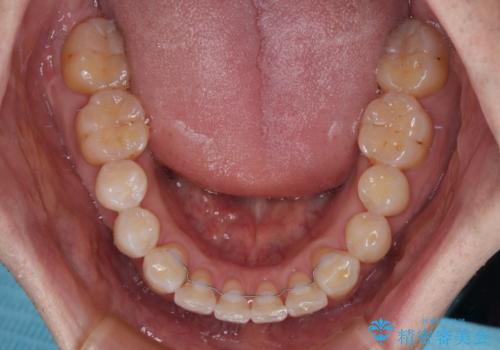

- 以前矯正治療を行ったものの、思い通りの仕上がりではなく、更には後戻りが気になってきたとのことで来院された患者様です。

上顎右側の第一小臼歯が動きにくい歯であり、以前矯正治療を行った際に傾斜した位置のまま終了したことと、それに伴い後戻りで歯列が波打っているようになっていることを大変気にしていらっしゃいました。

咬合平面改善のため、アンカースクリューを多用し、ワイヤー装置にて矯正治療を行うこととしました。